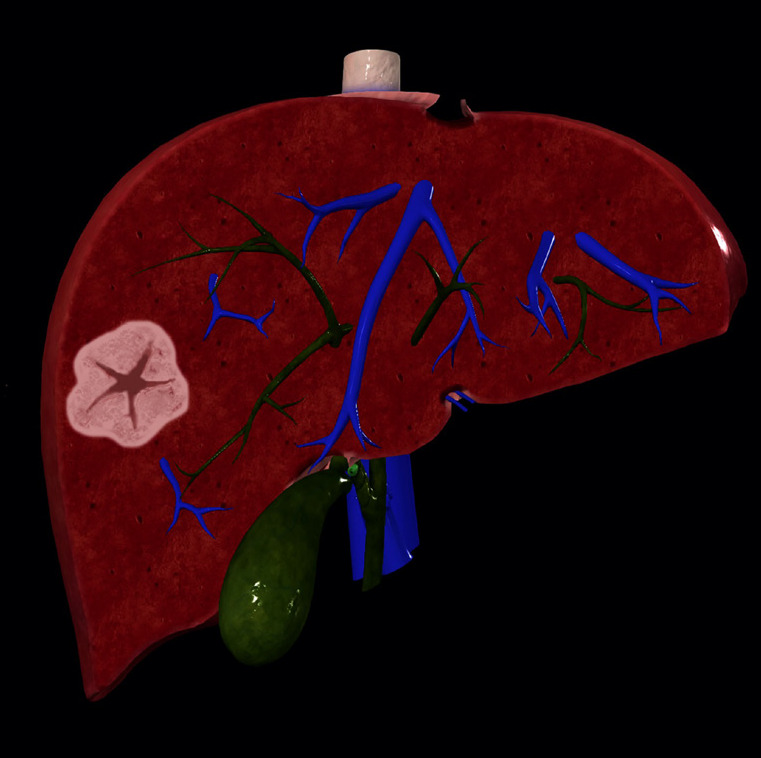

目的:本研究旨在评价人工智能(AI)在磁共振成像(MRI)诊断肝脏局灶性结节性增生(FNH)中的有效性,并与放射科医生进行比较。方法:在第一阶段的研究中,使用分割程序对60例患者(30例FNH患者和30例无病变或非FNH病变患者)的mri进行处理,并引入AI模型。在学习过程之后,将人工智能模型没有经验的42名不同患者的核磁共振成像引入系统。此外,一名放射科住院医师和一名放射科专家评估了具有相同MR序列的患者。敏感性和特异性值均来自所有三篇综述。结果:AI模型的敏感性为0.769,特异性为0.966,阳性预测值为0.909,阴性预测值为0.903。敏感性和特异性值高于放射科住院医师,低于放射科专科医师。专家与人工智能模型的结果显示出良好的一致性水平,kappa (κ)值为0.777。结论:人工智能设备诊断FNH的敏感性、特异性、PPV、NPV均高于放射科住院医师,低于放射科专科医师。随着对肝脏不同特定病变的进一步研究,人工智能模型有望在未来能够高精度地诊断每种肝脏病变。临床意义:研究人工智能为放射图像提供辅助或自动解释,并提供准确和可重复的成像诊断。

Purpose: This study aimed to evaluate the effectiveness of artificial intelligence (AI) in diagnosing focal nodular hyperplasia (FNH) of the liver using magnetic resonance imaging (MRI) and compare its performance with that of radiologists.

Conclusion: For the diagnosis of FNH, the sensitivity, specificity, PPV, and NPV of the AI device were higher than those of the radiology resident and lower than those of the radiology specialist. With additional studies focused on different specific lesions of the liver, AI models are expected to be able to diagnose each liver lesion with high accuracy in the future.